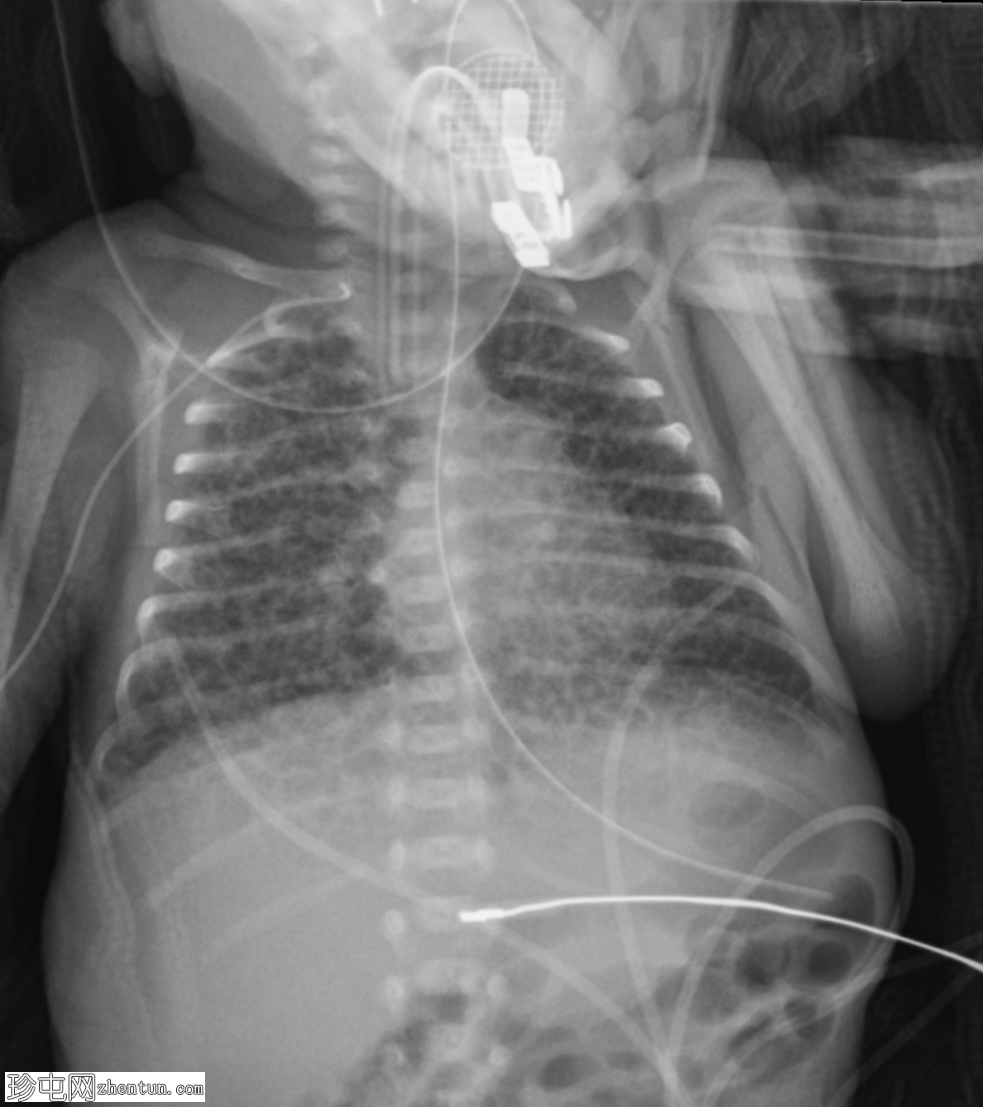

早产儿(胎龄23周),呼吸窘迫。

年龄:6天

性别:男

内可见弥漫性粗化网状阴影和散在的透亮影。

肺过度扩张。

无胸腔积液或气胸。

心纵隔轮廓正常。

气管插管终止于T3椎体水平。

经食管营养管终止于预期的胃部区域。

右上肢PICC导管向头侧延伸,疑似终止于右侧颈内静脉。

本例疑似肺间质气肿(PIE)病例。

在适当的临床情况下,如果发现粗化网状阴影并伴有透亮影,则为PIE的特征。这种疾病几乎仅见于需要机械通气的新生儿。这名孕23周出生并入住新生儿重症监护病房 (NICU) 的婴儿,面临多种早产相关并发症的高风险,包括肺动脉高压 (PIE)、呼吸窘迫综合征 (RDS) 和支气管肺发育不良 (BPD)。在本例中,患者随后患上了呼吸窘迫综合征 (RDS),并最终发展为支气管肺发育不良 (BPD)。